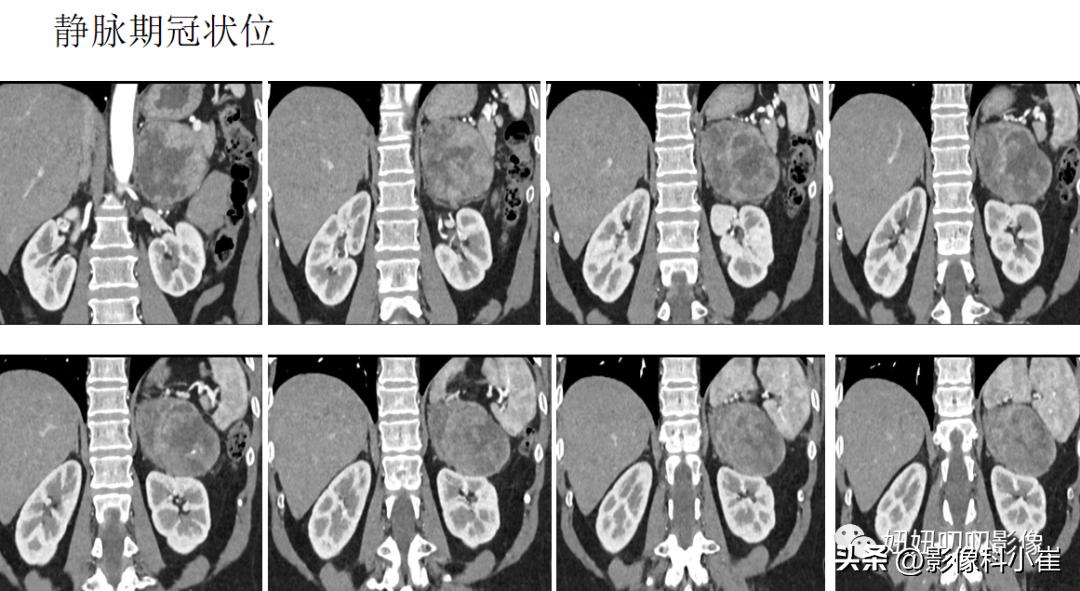

病史:

女,57岁,主诉:查体发现左肾上腺占位10天。最近测血压最高150/85mmHg。

影像描述:

左侧肾上腺区见一团块状等长T1 等长T2 混杂信号,边界尚清,DWI示部分弥散受限,T1 反相位信号未见明显减低,最大截面约9.7X7.0X71,其内见点状短T2 信号,增强扫描呈明显渐进性不均匀强化,邻近组织受压。右侧肾上腺形态、信号未见异常,增强后未见异常强化。双肾见小圆形长T1长T2 信号,边界尚清,增强扫描未见明显异常强化。腹腔及腹膜后未见明显增大淋巴结。腹腔内未见明显液体信号灶。